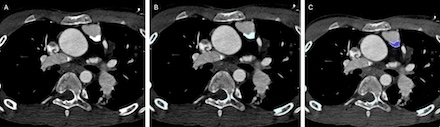

Retrospective, single center review of CT scans from patients with CHD who underwent surgical repair between 2014 and 2021. Patients with CC were identified, and cvi42® (Circle Cardiovascular Imaging, Inc) was used to quantify CC (Figure 1). These patients were age-matched to controls. Operative details and post-operative cardiac complications (atrial arrhythmias, ventricular arrhythmias, myocardial infarction, hospitalization for heart failure and cardiac arrest) were compared. Measurements were independently performed by a medical student and an attending physician, with the attending physician repeating all calculations.